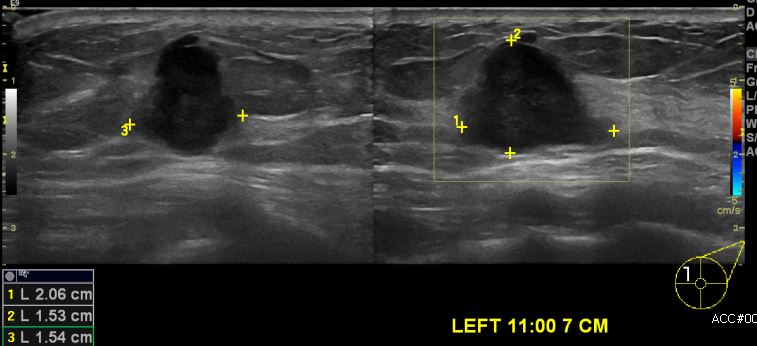

건강검진상 이상 소견으로 내원하신 70대 여성분으로 좌측 11시 방향에서 7cm 떨어진

거리에 의심 스러운 혹 조직검사 시행하여 좌측 침윤성 유관암 진단 되었습니다.